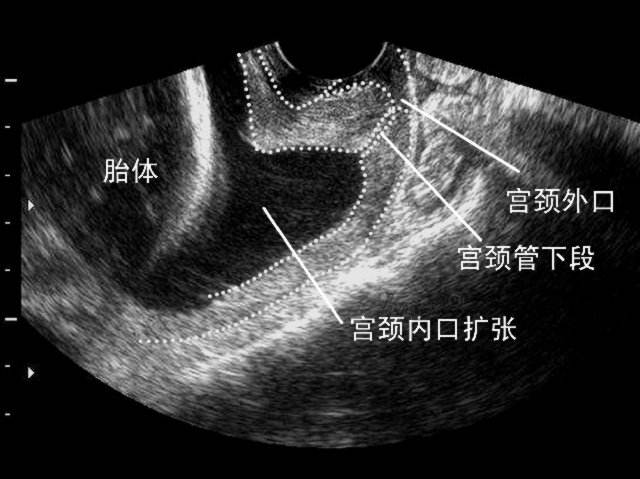

在孕中期,宫缩较少或没有的情况下,突然出现的宫颈变短和扩张。

下列辅助检查符合一项者即可诊断:孕前子宫输卵管造影证实宫颈机能不全,宫颈管宽度>6毫米,呈病理性扩张;非孕期用8号宫颈扩张器伸入宫颈内门毫无阻力;非孕期B超显示宫颈缩短且≤25毫米或呈漏斗状;临床证明有明显的宫颈损伤史.

以流产病史为指征行宫颈环扎术(也称预防性宫颈环扎术)的患者,是基于流产病史诊断为宫颈机能不全,有指征行宫颈环扎术,通常在孕13-14周进行环扎术。试验表明,宫颈环扎术更适合于曾有3次或更多妊娠中晚期流产或早产的高风险患者。对于无产兆而出现进行性宫颈扩张的孕妇,是以体格检查诊断为指征的宫颈环扎术的对象,也称急诊或补救性宫颈环扎术。有限的数据表明去来查体排除子宫高反应性和羊胰脏感染,行急诊宫颈环扎术对单胎妊娠孕妇是有意义的。以超声诊断为指征(也称应激性或治疗性宫颈环扎术)的宫颈环扎术是在超声发现宫颈管长度<25毫米,内口呈“鸟嘴状”改变时手术。大多数有宫颈机能不全风险的患者在孕中期可以行一系列阴道超声监测来安全指导妊娠,建议有高风险患者在孕16-24周期间密切行超声监测。实验证实对于单胎妊娠孕妇,合并37周前自然早产史,此次妊娠不足孕24周即出现宫颈长度<25毫米,行宫颈环扎术是有效的,可显著降阳氐早产率,改善新生儿患病率和死亡率。对于同时合并早产史和宫颈长度缩短的孕妇,可以考虑行宫颈环扎术。另外,近年来,越来越多的宫颈机能不全患者选择在备孕前实施宫颈环扎术。这个时期实施手术不会影响术后的妊娠,降低了妊娠期手术孕妇和新生儿的并发症发生率。